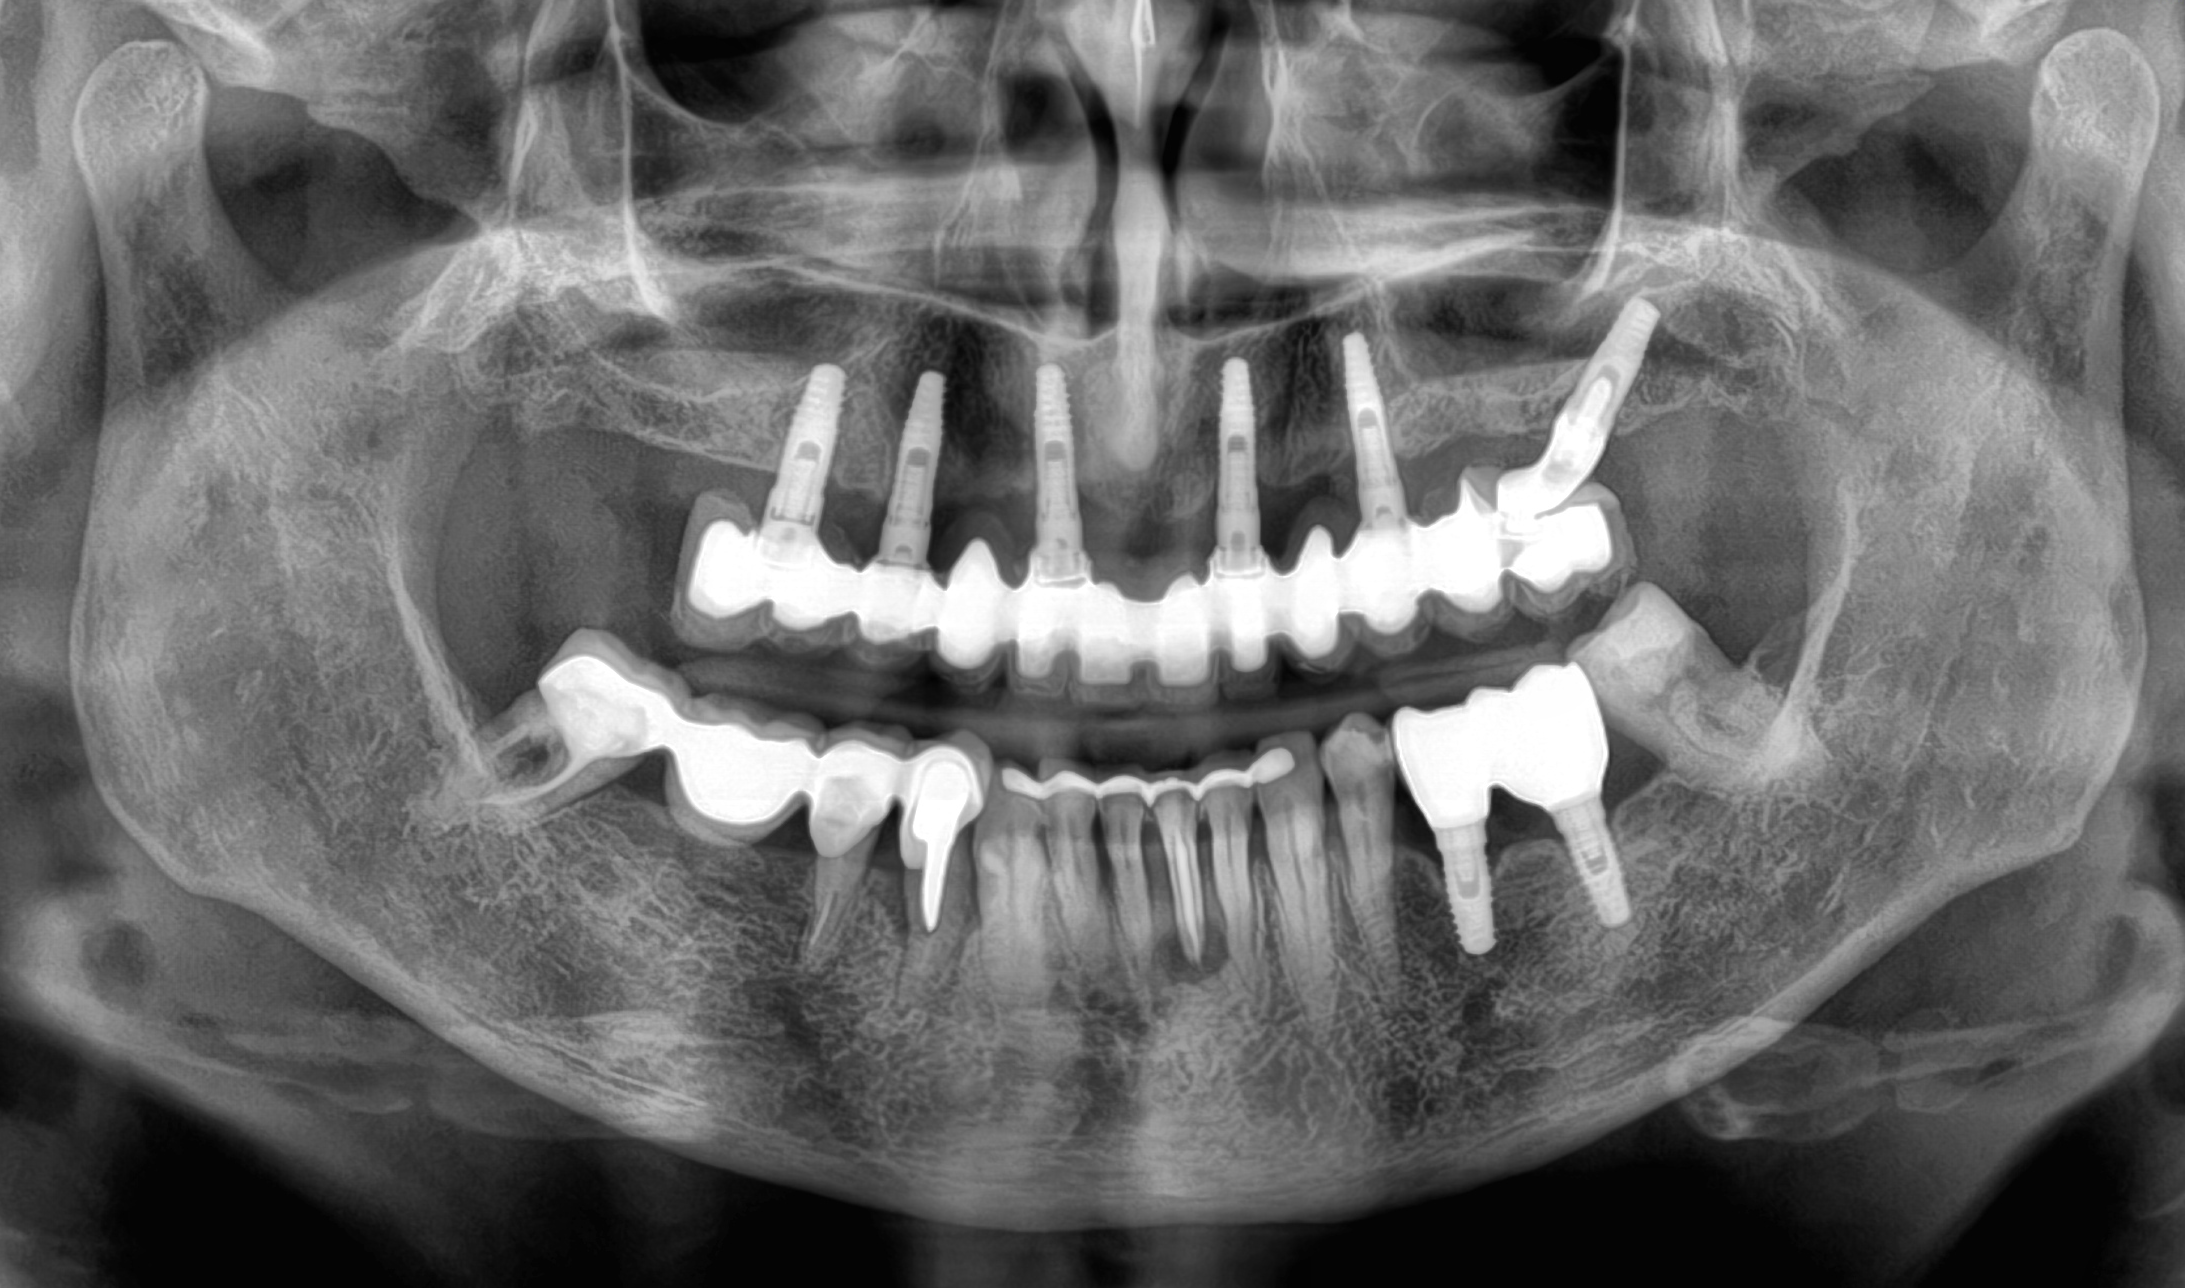

Caso 5

A causa di vari problemi di salute, la paziente si trova in una situazione di edentulia completa in entrambe le arcate. Le attuali protesi mobili sono per lei fonte di forte insicurezza a causa della loro mobilità. Nonostante la scarsità di osso mascellare e la presenza di viti di osteosintesi nella mandibola si procede con una riabilitazione fissa su entrambe le arcate combinando impianti tradizionali (mandibola) con impianti iuta-gengivali, nella mascella.

DOPO